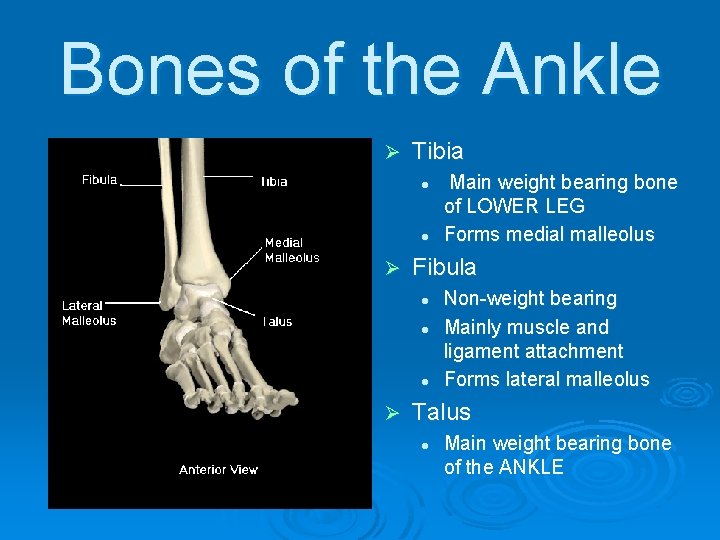

Bones of the Ankle Ø Tibia l l Ø Fibula l l l Ø Main weight bearing bone of LOWER LEG Forms medial malleolus Non-weight bearing Mainly muscle and ligament attachment Forms lateral malleolus Talus l Main weight bearing bone of the ANKLE